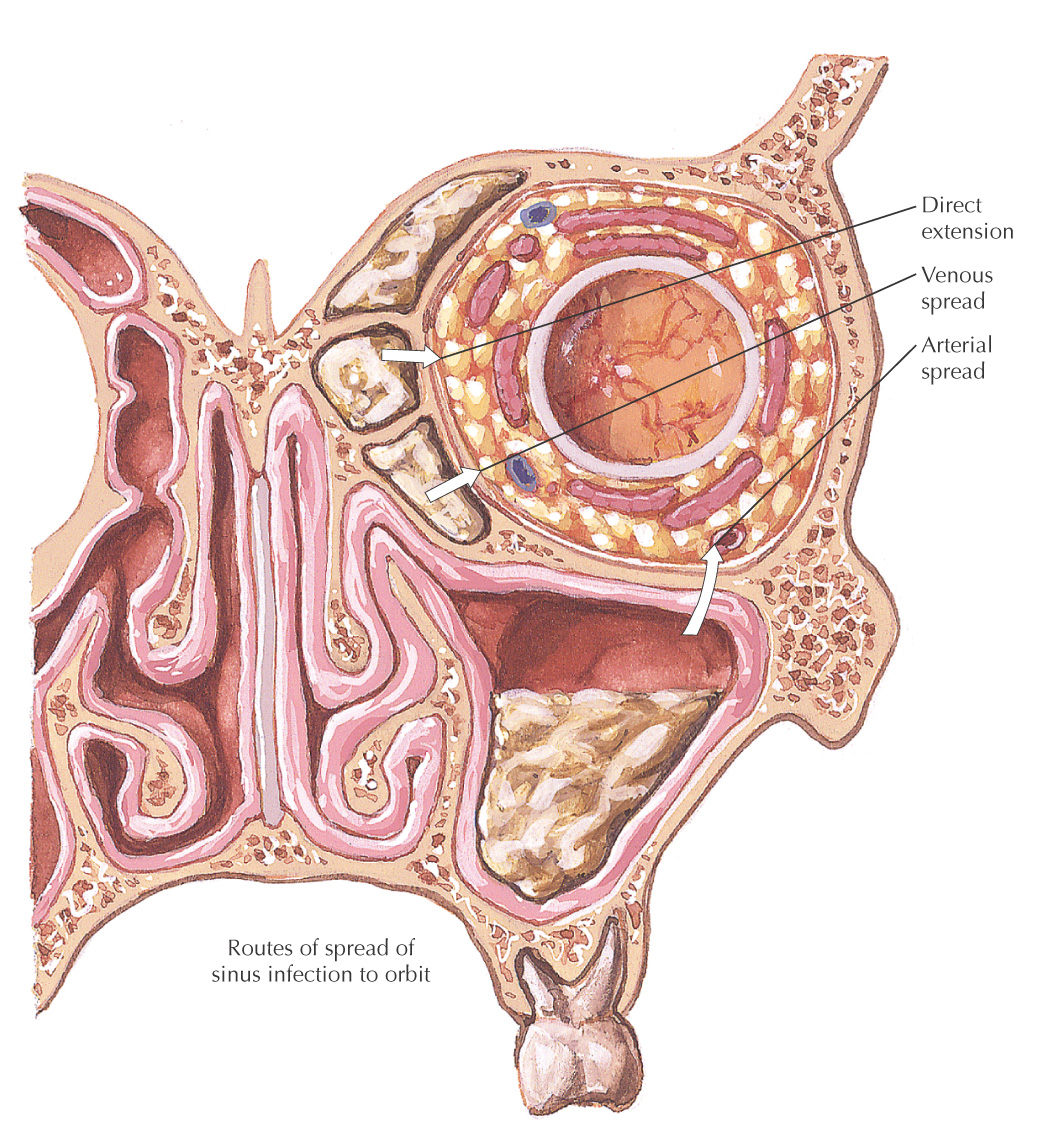

• Ethmoid: potential complications include meningitis and orbital cellulitis

• Superior: orbit, infraorbital nerve and vessels